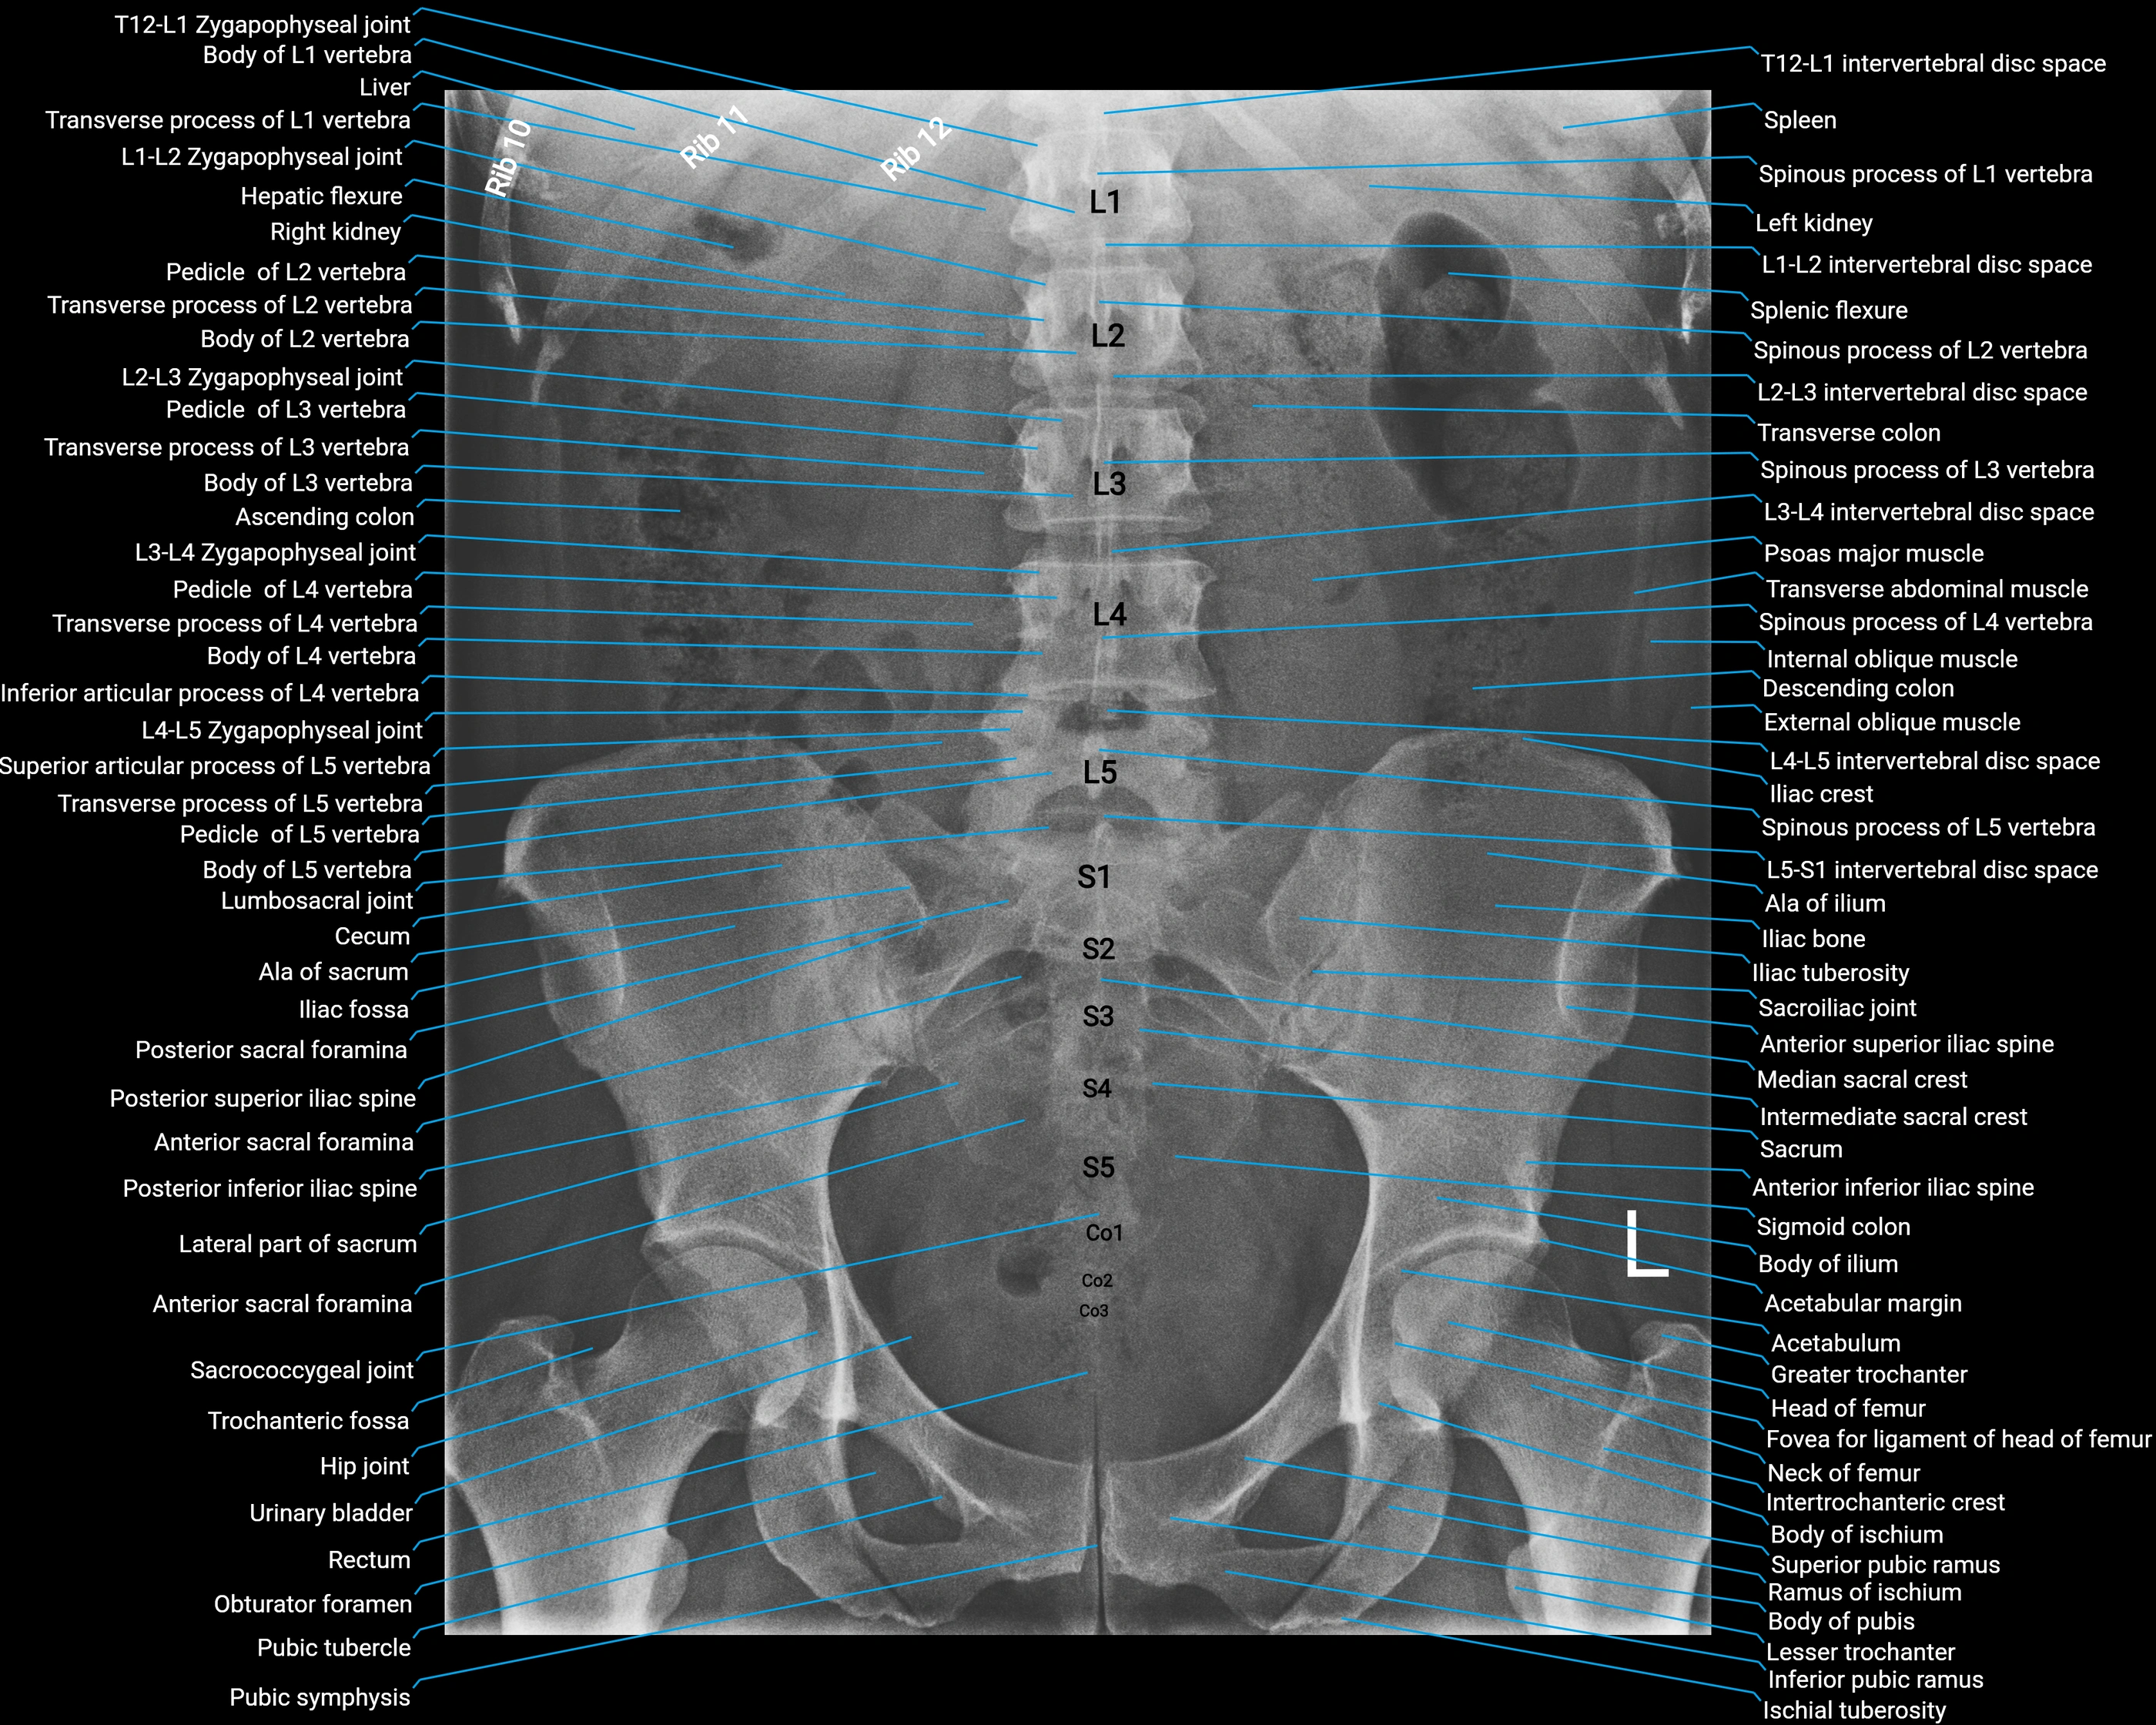

CT Appearance

Non-Contrast CT:

• Accessory process appears as a small bony outgrowth at the posterior base of the transverse process

• Clearly visualized due to high resolution of cortical bone

• Useful for detecting fractures, bony hypertrophy, or congenital variations